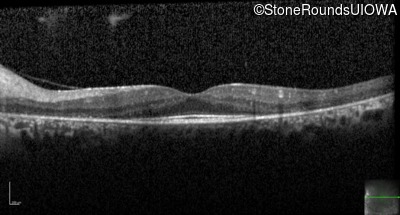

Optical Coherence Tomography - Right - 20/25

Exemplar / OCT Stack